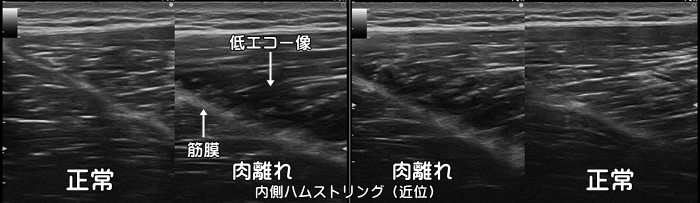

ハムストリングス肉離れ

短距離ランナーに多い大腿後面、ハムストリングスの肉離れです。中等症や重症例では血腫の確認が可能です。軽症例の場合はエコーで異常は確認できません。上記の症例は受傷後3~4ヶ月しても痛みが取れないため受診。通常肉眼での皮下出血は受傷から2~3日後に確認できます。